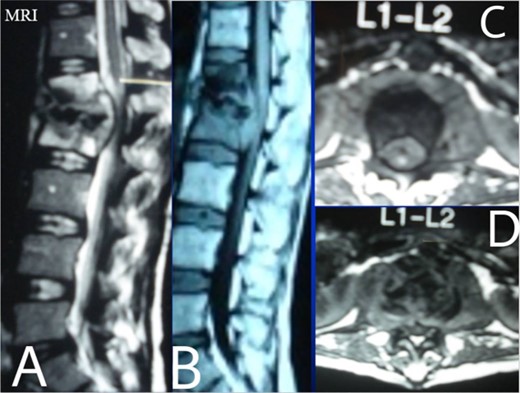

Lumbar T1 and T2 consistent with an abscess at the L1–2 vertebral level. (A) and (B) showed that the height of the L1 and L2 vertebral bodies was markedly reduced and the dural sac and spinal cord were severely compressed by an abscess posterior to the vertebral body. (C and D) Axial T1 shows a well-defined paraspinal abscess. The anterior epidural abscess compresses the spinal cord.